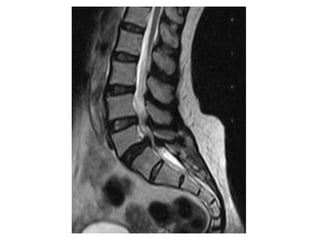

Lumbar MRI (sagittal view)

Cauda Equina Syndrome A clinical syndrome due to compression of lumbo-sacral spinal nerves Clinically, radicular pain, uni or bilateral Motor weakness in variable myotomes and sensory loss Perineal numbness Loss of anal tone Loss of bladder function leading to retention Impotence and sexual dysfunction

Complete or incomplete CES Complete CES Objective loss of perineal sensation Bladder retention Patulous anus Incomplete Altered sensation, loss of desire to void and poor stream

Cauda equina syndrome can be caused by anything which compresses the lumbo-sacral nerves  (the cauda equina) Big disc prolapses in young people Tumours which can be primary or metastatic Infection including discitis and spinal abscesses Trauma bone fragments and blood clots Ligamentous hypertrophy in elderly with canal stenosis